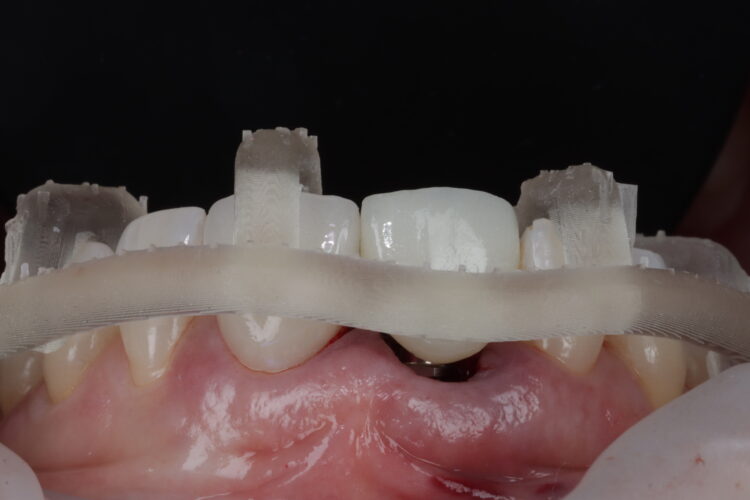

An intraoral scan was taken, including the entire palate to provide a precise reference for the CBCT scan. This enabled the accurate merging of the intraoral and CBCT scans to create a diagnostic wax-up for the provisional restoration.

Smile Cloud software with AI-driven smile design features was used to assist treatment planning and provide short animations for use in patient communication. The same data was put into SMOP software to design the surgical guide, which is essential to optimise primary stability for immediate loading.

Two temporaries were requested from the laboratory. One was fabricated from the SMOP guide affording high visualisation to increase precision of fit. The second temporary had a stent that sat over the incisal edges, which could be used to confirm accurate positioning.